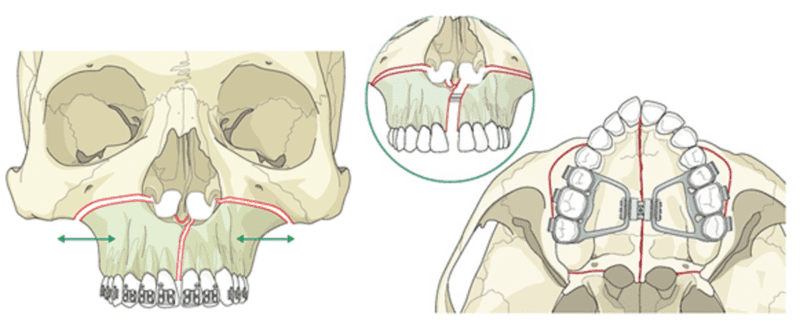

In severe maxillary transverse constriction or after growth has ceased, orthodontic treatment alone is not sufficient for successful expansion. These cases require a combination of surgery and orthodontic treatment, i.e. Surgically Assisted Rapid Maxillary Expansion (SARME).

SARME

Surgically assisted palatal expansion (SARPE) that cuts the bone for reducing the resistance without completely releasing the maxillary segments succeeded by jackscrew rapid expansion is another possible treatment approach in adults with narrow maxilla.

Before surgery, fixed appliances can be used to move apart the roots of the central incisors to prevent the damage of roots by a midline maxillary surgical cut. Expansion is typically carried out at a rate of 0.5 mm a day. Due to the inelasticity of the palatal mucoperiosteum there will be more chances of relapse after surgical correction, so overcorrection is required to compensate the relapse.

Technique for SARME– Hyrax expander is cemented onto the maxillary first molars and premolars before the surgical treatment, which includes bilateral osteotomies performed from the piriform rims to the pterygomaxillary junction. A screw expansion of approximately 2 mm is performed directly after surgery, and the screw is then activated once or twice a day until the desired expansion has been achieved.